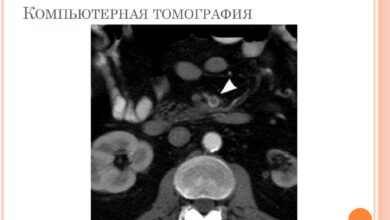

Рентген диагностика Рентген суставов является одним из основных методов визуализации для выявления артрита. Этот метод позволяет врачам получить детальные изображения…